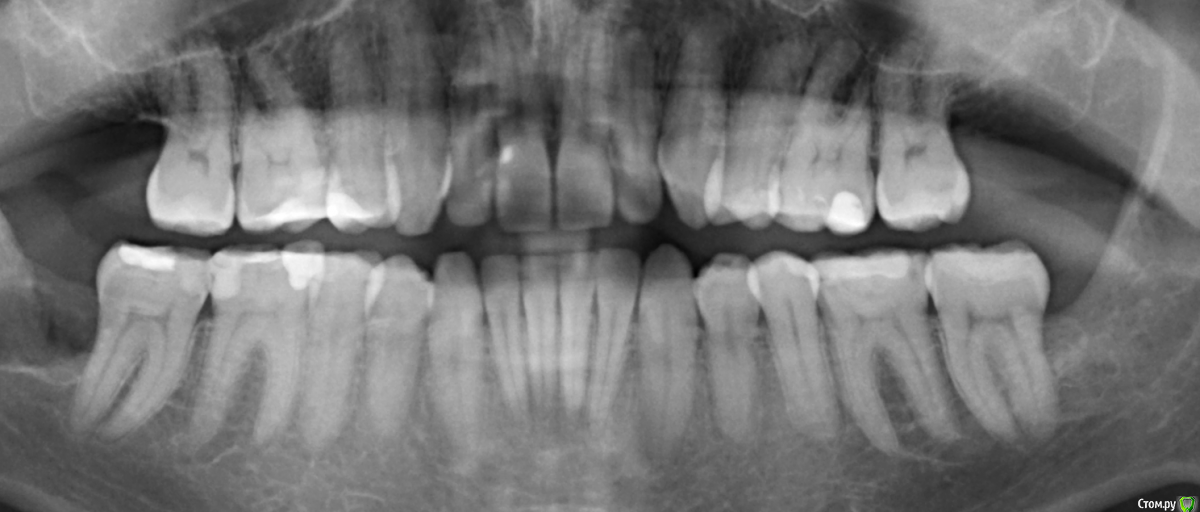

michaelks7 Опубликовано 2 февраля, 2019 Поделиться Опубликовано 2 февраля, 2019 Добрый день Предыстория: 14 числа было сложное удаление нижней 8ки10 дней антибиотиков + ~ 12 дней обезбаливающих ( с понижением силы/дозировок) Несколько дней назад после мороза хлебнул горячеватый кофе - заныл передний резец или около негоплюс на нижней челюсти периодически появляются ноющие ощущения в области 11-12 зубов(параллельно верхним с пломбами) - они ни разу не лечились - без пломбоколо них воспалена деснав моей бывшей клинике даже снимка не сделали - ограничились внешним осмотром, сказали чувствительность зубовв другой клинике посмотрели панорамный , также сделали прицельный. Вердикт , кариес под пломбами между зубов -перелечиватьпро нижние сказали все нормально, снимок делали, на нем тоже криминала не увидели. Сказали проблема скорее всего в зубном камне под деснойплюс под перелечивание отправили нижние правую 7 и левую 6 не могли бы вы взглянуть насколько все так как сказали или потенциальных проблем больше/меньше - появился вопрос с выбором стоматолога. В старую клинику не хочу возвращаться.и неясный момент с нижними 11-12 прикладываю панорамный снимок и прицельный передних с пломбамиЗаранее спасибо Ссылка на комментарий

michaelks7 Опубликовано 4 февраля, 2019 Автор Поделиться Опубликовано 4 февраля, 2019 добрый день0 откликоввзгляните пожалуйста , основные жалобы 21-22 зуб несколько дней назад была разовая реакция на температуру. после этого периодически появляются слабые ноющие ощущения. вторичный кариес может такое вызывать или грешить сразу на пульпит?про перелечивание зубов 16/17/26/27/36/37 , какие из них на ваш взгляд требуют повторного лечения?спасибо, надеюсь на получение ответа Ссылка на комментарий

red_butler Опубликовано 4 февраля, 2019 Поделиться Опубликовано 4 февраля, 2019 на снимках кариеса не увидел, покажите фото зубов Ссылка на комментарий